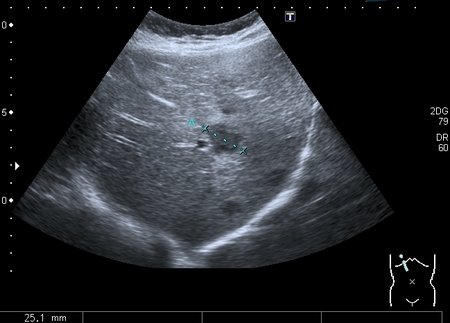

Девочка 13 лет, в течение 2-х недель температура до 38, СОЭ - 40 мм\ч, СРБ - 30.

На УЗИ: Учитывая клинику, лабораторные данные поставил гистиоцитарную инфильтрацию печени и селезёнки при генерализованной инфекции. Несколько раз встречался со схожими случаями, на фоне антибиотикотерапии изменения уходили. Но в данном случае девочка уже получала антибиотики в течение недели, на этом фоне не получено ни клинического , ни лабораторного улучшения, а на УЗИ очаги стали больше. Нужно ли расширять дифференциально -диагностический ряд? Ваши мнения

Имхо, по УЗ-семиотике - множественные небольшие абсцессы.

Мне нравится информация по данной патологии из видаровского "Клинического руководства по ультразвуковой диагностике в педатрии". Там данные изменения носят название очаговых поражений инфекционной этиологии (иерсиниоз, псевдотуберкулёз, токсокароз, хламидиоз и др.). Но инфекционисты, проведя ИФА с очень скудным набором диагностикумов и получив отрицательный результат, так же говорят, что это "не их".